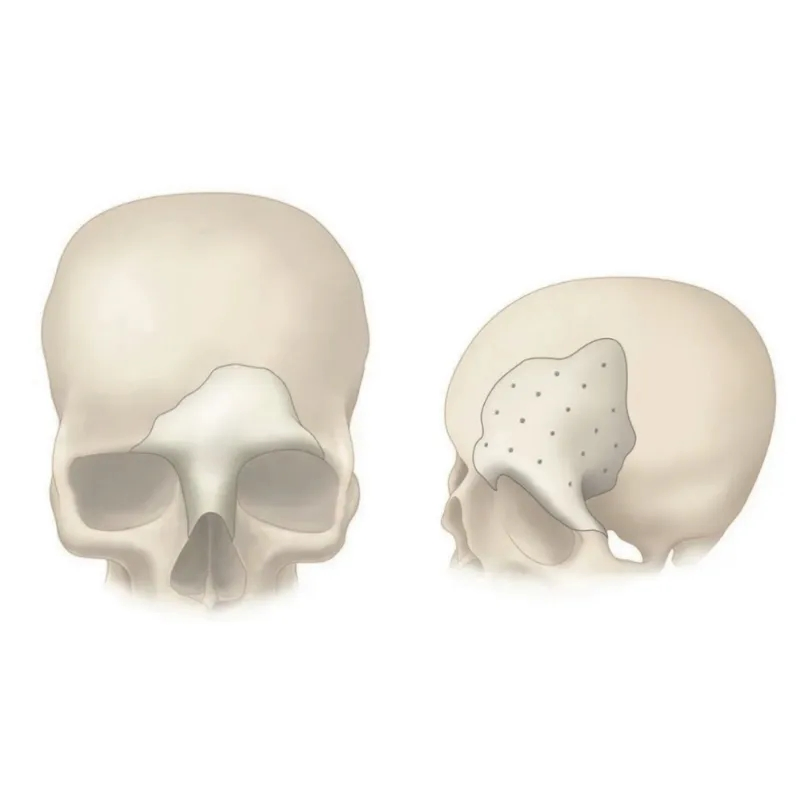

PEEK can be designed and provided in single or multiple pieces with just-fit or over-lay concept as indicated above. Additionally, this patient specific implant can be reliably fixated using cranial fixation systems.

Perfect Contour Reconstruction

Precisely match the natural contour and convenient to implant. CAD/CAM technology allows to restore the defect models and reconstruct the natural contour of the brain.